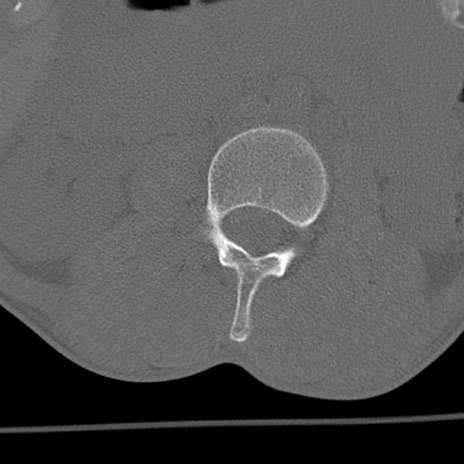

症例3 腰椎CT(横断像)

腰椎CT